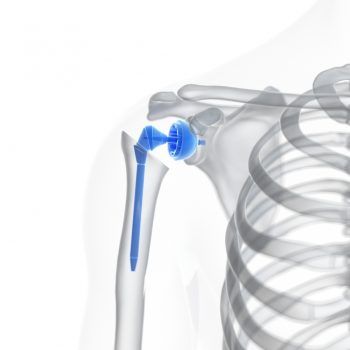

Schouderprothese (nieuwe schouder)

Een schouderprothese is een kunstmatige vervanging van een aangedane schouder. Een knie- of heupprothese kent iedereen wel. Vervanging van de schouder door een prothese is veel minder bekend. Een prothese wordt voornamelijk gebruikt wanneer een gewricht ernstig versleten is (artrose).

Verschillende schouderprotheses

Er zijn vier verschillende schouderprotheses. Welke prothese wordt gebruikt is afhankelijk van de conditie van de schouder. De orthopedisch chirurg onderzoekt wat de staat van de schouder is en neemt hierin de beslissing.

De vier protheses zijn:

- Totale schouderprothese.

- Halve schouderprothese.

Totale schouderprothese

Bij een totale schouderprothese wordt zowel de schouderkop als de schouderkom vervangen.

- De schouderkop wordt vervangen door een metalen kop met een lange steel.

- De steel wordt in de bovenarm vast gezet. Dit kan met cement of door inklemming in het bot.

- De schouderkom wordt vervangen door een kunststof of metalen kom.

- Ook deze komprothese kan met cement of door ingroeiing vastgezet worden.

Halve prothese

Een halve prothese wordt gebruikt wanneer alleen de schouderkop beschadigd is.

- De schouderkop wordt vervangen door een nieuwe kop van metaal.

- Deze steel van de nieuwe schouderkop wordt in de bovenarm geplaatst.